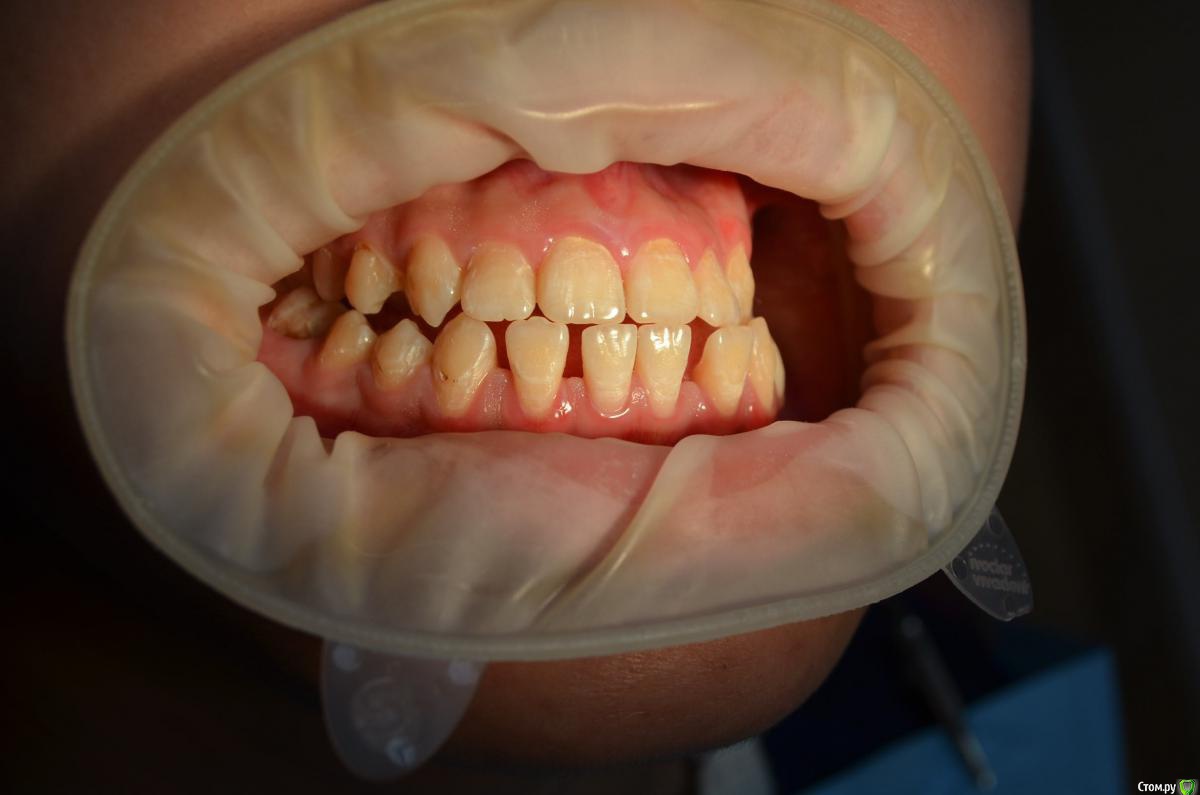

Пациентке 16 лет носила брекеты 4 года (переносила), нижний фронт зубов подвижен, слизистая воспалена, тремы на н.ч, множественный кариес под брекетами после снятия, сейчас на этапе эндолечения. Помогите советами как правильно и с чего начать , на в.ч. поставил ретейнер, на нижней пока идет терапевтическое лечение. ТРГ нету